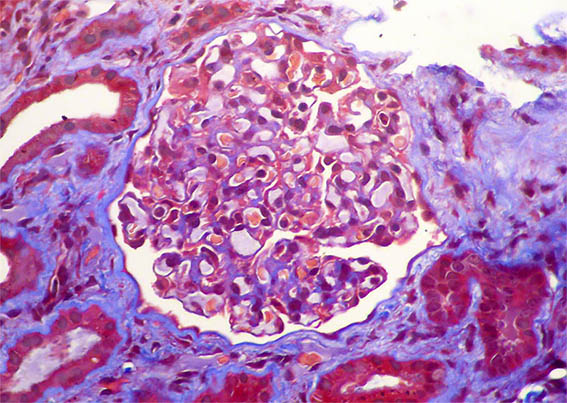

Figura 4. Tricrómico de Masson, X400.